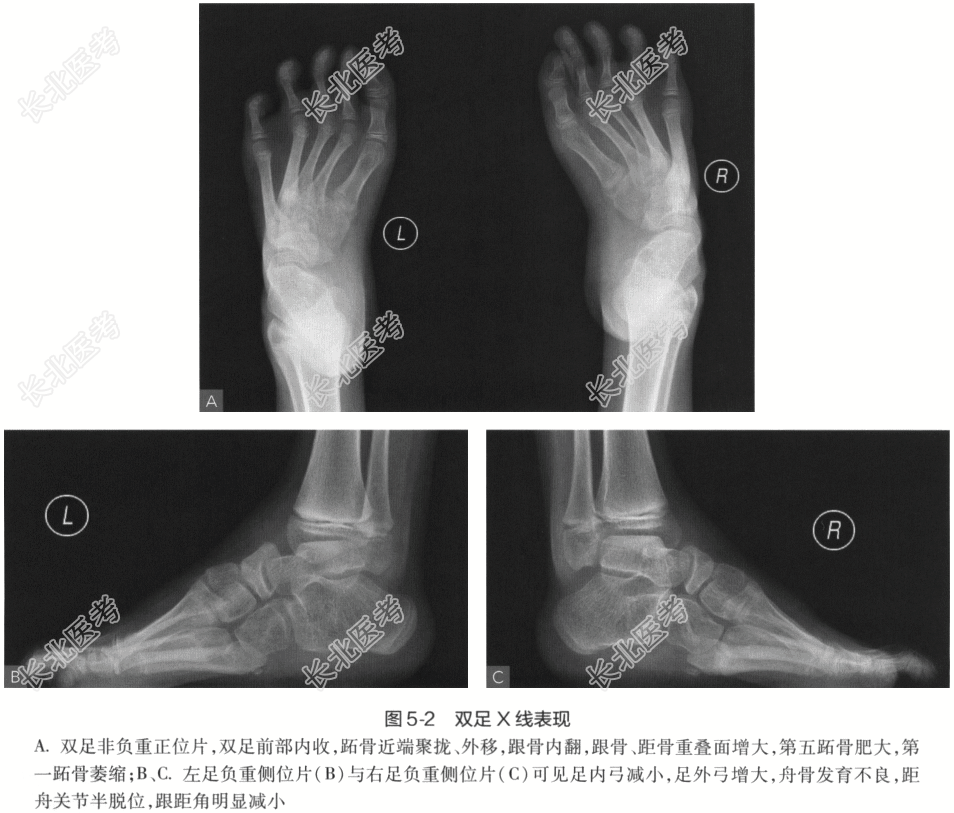

- [材料题] 患者,女性,8岁。主诉:双足内收、内翻畸形,呈马蹄状,且随年龄增长逐渐加重。现病史:双足明显内翻、内收畸形,跟腱及跖筋膜挛缩、紧张,双足距骨、骰骨均脱位,骰骨外凸形成滑囊,双足跟内翻,尖小,双足背外侧着地负重,内踝深陷,背伸活动功能障碍,不能独立行走,双小腿肌肉萎缩。影像学检查: